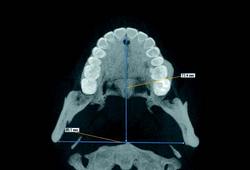

3-D software can shade images to differentiate varying densities of facial structures. Grayscale shading provides the ability to view the relationships of common internal anatomy. Traditional CT imaging renders an 8-bit grayscale (256 shades) or 12-bit grayscale (4,096 shades). Present-day scanners render images in 14-bit grayscale, providing 16,384 shades. Color coding the image by density further distinguishes anatomical structures, enabling the clinician to view pertinent anatomy while planning implant cases, such as nerves and nasal cavities, and mandibular and maxillary dimensions. Segmentation literally cuts the volume rendering, conceding top views, side views, and CT slices that produce unlimited axial, coronal and sagittal views. CBCT slices are as thin as 0.1 mm, compared to 1 mm for a conventional fan CT scan.

CBCT imaging is the ideal radiological modality for implantology due to the high quality of the produced images, software capabilities, and lower doses of radiation exposure. Two of the hottest topics regarding CBCT and implantology are virtual surgery planning and surgical guides. A virtual surgery can be performed with special software applications that enable dentists to evaluate the quality of bone through density shading and dimensions of bone can be recorded accurately with 1:1 measurement tools. It identifies common internal anatomy needed to evaluate implant placement including the jaw boundaries, adjacent teeth, nasal fossa, mandibular canal, maxillary sinus, mental foramen, and incisive canal. It also detects pathology to be avoided for implant health. Therefore, before the surgery, the clinician can confirm the appropriate implant size, location and angulation, and that plan can be fed to a 3-D printer to produce a surgical guide or stent for use during the actual surgery.